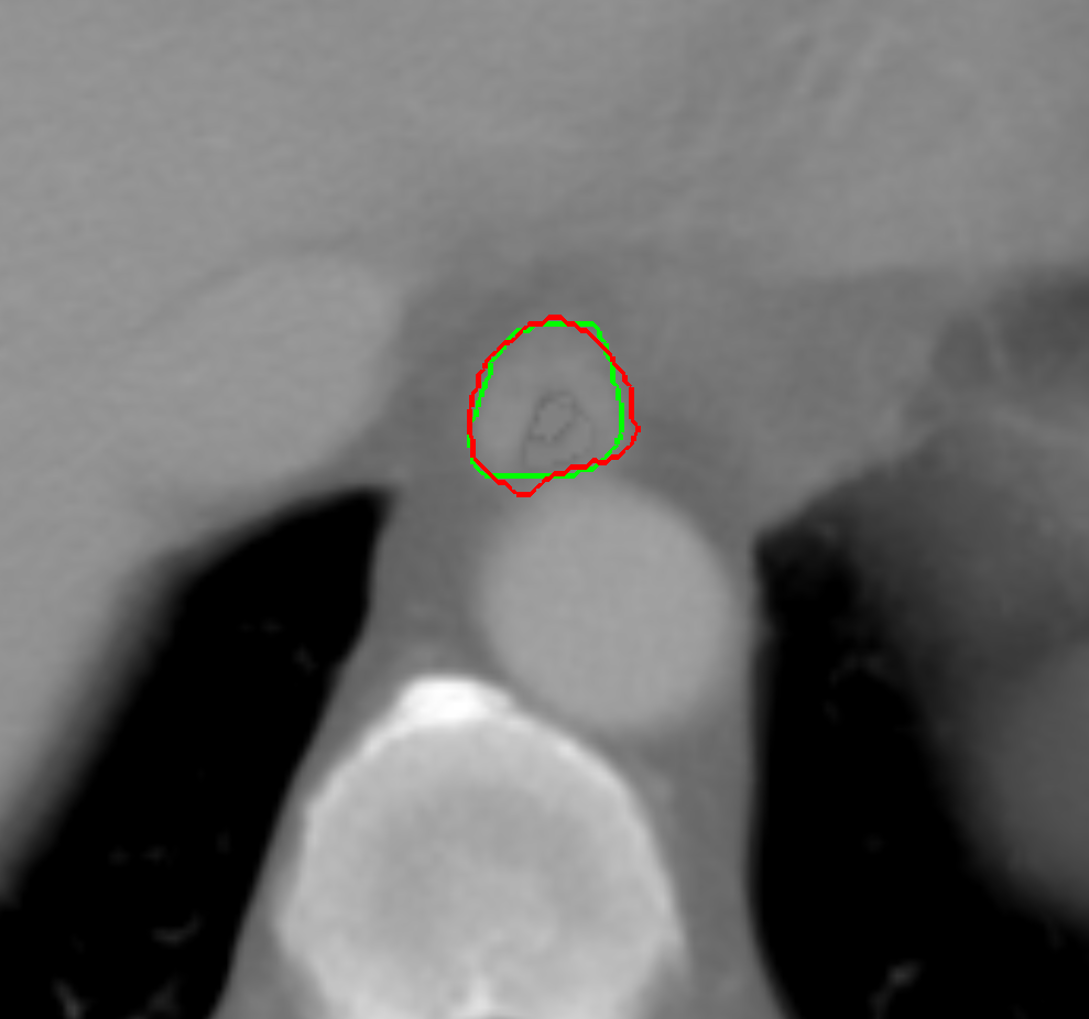

Visual results of our algorithm compared to the reference contour for 6 cases in axial and sagittal view are depicted in Fig. 5. From the sagittal views it can be observed that manual contours are not as smooth as the automatic contours, which could be due to the breathing artifacts. The use of convolutions and post-processing in 3D aids at processing information of the 3D context through several slices, which is reflected in the smoother automatic contours shown in these images. On the other hand, from the axial views we can realize that, despite of the similarity with respect to neighboring tissues, and heterogeneity of the inner region of the esophagus, our automatic system provides contours that are comparable with the reference standard.

Refer to caption a) clinical case 09 sagittal view Refer to caption b) clinical case 13 sagittal view Refer to caption c) clinical case 20 sagittal view

Refer to caption d) clinical case 09 axial view Refer to caption e) clinical case 13 axial view Refer to caption f) clinical case 20 axial view

Refer to caption g) public case 01 sagittal view Refer to caption h) public case 12 sagittal view Refer to caption i) public case 24 sagittal view

Refer to caption j) public case 01 axial view Refer to caption k) public case 12 axial view Refer to caption l) public case 24 axial view

Figure 5: Contouring results for 6 cases in different views. The green line indicates the reference standard, the red line depicts the contour generated by the proposed algorithm.